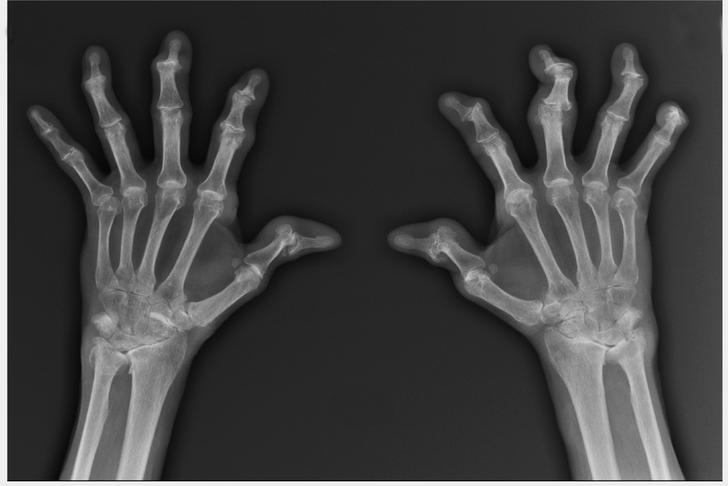

Joint Deformity

In advanced cases of osteoarthritis, the affected joints may become visibly deformed. This can be due to a combination of bone spurs, loss of cartilage, and joint instability[[2]].